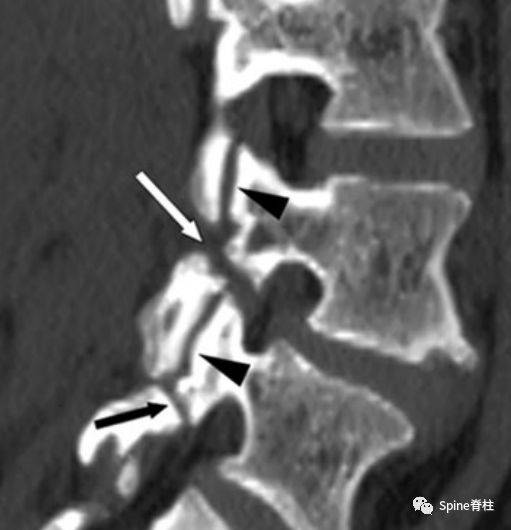

硬化显著,矢状位重组显示腰5椎弓峡部崩裂(长↑)china-radiology审稿